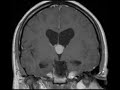

Colloid Cyst

These MR images show a T1 hyperintense, T2 hypointense unilocular mass located in the foramen of Monro. The mass does not enhance or restrict diffusion. This location and imaging appearance are classic for a colloid cyst. These patients can present with positional headaches and/or obstructive hydrocephalus. If symptomatic, these lesions are removed surgically. Aspiration may fail if the lesion is too viscous as might be the case with this lesion which is T2 hypointense.